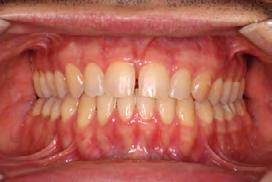

4). Archwires were upgraded incrementally into 19 x 25 SS. Once the bite was completely closed, the patient was referred to the myofunctional therapist to begin treatment. Eight sessions of myofunctional exercises were performed, focusing on muscle building, toning, synchronicity and awareness. Improvement in correct chewing, swallowing and resting postures of the lip and tongue were addressed. All appliances were removed 21 months after initial insertion (Figure 5), and the patient was referred to a re-

storative dentist for veneers on the maxillary central incisors; the patient opted for gold veneers (Figure 6). Clear removable retainers were inserted with a fixed mandibular retainer canine-to-canine.

Treatment Results

The patient finished with Class I occlusion, ideal overbite and overjet. The arches are co-

Figure 5. Final records.

ordinated, lateral open bite closed and occlusal cants leveled. From the frontal cephalometric tracings, maxillary width increased from 58 mm to 69 mm. From the lateral cephalometric tracing, the incisor angulations remained unchanged. The final report from the myofunctional therapist indicated the patient eliminated the bilateral posterior tongue-thrust swallowing pattern with saliva, liquid and solid swallows. Correct swallowing mechanics were demonstrated while sipping/gulping liquids from a cup. His day and nighttime tongue-resting postures were reported to be on his incisive papilla, with lateral margins lightly suctioned into the upper arch. Lips were closed and competent diurnally and nocturnally.

Most recent records are two years after removal of the orthodontic appliances, demonstrating the stability of the results (Figure 7).